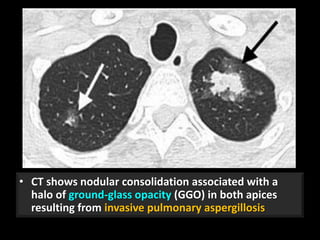

Invasive pulmonary

aspergillosis

• CT shows nodular consolidation associated with a

halo of ground-glass opacity (GGO) in both apices

resulting from invasive pulmonary aspergillosis

• This halo represents hemorrhage.

• When seen in leukemic patients, is highly suggestive

of the diagnosis of invasive pulmonary aspergillosis.